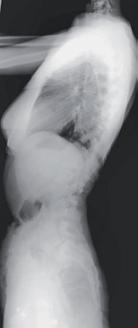

RYCINA 34.14.

Radiogram kręgosłupa w projekcji bocznej – stan przedoperacyjny.